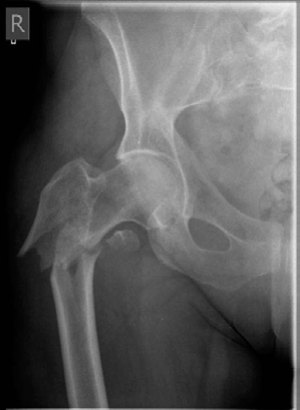

A 78-year-old woman fell out of her bed and sus- tained this injury. She is in reasonably good health and independently mobile, able to care for herself and do her own shopping. (Figure 8.9.)

CANDIDATE : This is an AP radiograph of the right hip showing a reverse-obliquity inter-trochanteric fracture with subtrochanteric extension. The lesser trochanter is proximally displaced with loss of the medial buttress. I would like to see a lateral radiograph, however, based on just the AP view, it is an unstable fracture pattern.

My management for this patient would start with a thorough assessment and optimization of her general medical condition. We need to exclude the possibility of pathological fracture, although the available radiograph shows no evidence of that.

I would obtain full-length radiographs of the femur. Provided she is fit and agrees to surgery, I would aim to manage this fracture operatively and I will do so as early as possible, preferably within

36 hours of admission [new NICE guidelines]. I would use a cephalomedullary device as this has shown better results rather than fixed-angle plating devices in this fracture configuration.1,2

Figure 8.9 Anteroposterior (AP) radiograph right femur demonstrating inter-trochanteric fracture.

EXAMINER : What can you see and how you going to manage her? CANDIDATE : This is an AP radiograph of the right hip showing a reverse-obliquity inter-trochanteric fracture with subtrochanteric extension. The lesser trochanter is proximally displaced with loss of the medial buttress. I would like to see a lateral radiograph, however, based on just the AP view, it is an unstable fracture pattern.